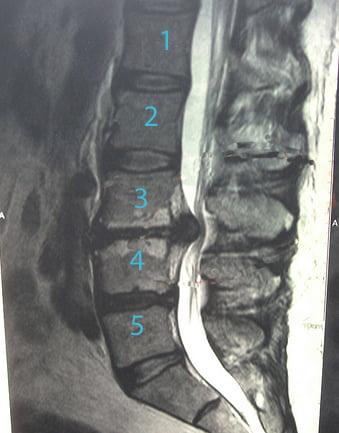

В диагнозе обязательно отражается, какой именно диск поражен грыжей. Для его обозначения используют специальную буквенно-цифровую систему.

Диск l4l5 отделяет 4 и 5 позвонок поясничного отдела (он обозначается латинской буквой l)

Аналогично диск л1л2 отделяет 1 и 2 позвонки поясницы, а l5s1 – 5 позвонок поясницы и 1 позвонок копчикового отдела. Есть свои обозначения и для позвонков шейного отдела – например, с5с6 отделяет 5 и 6 позвонки шеи. Однако там грыжа наблюдается реже всего ввиду небольшой нагрузки на шею, по сравнению с поясницей.

Для уточнения локализации грыжи или другого патологического процесса, его размеров, соотношения с окружающими тканями пациенту показаны точные инструментальные исследования — КТ, МРТ, МСКТ. При подготовке назначаются консультации узких специалистов.